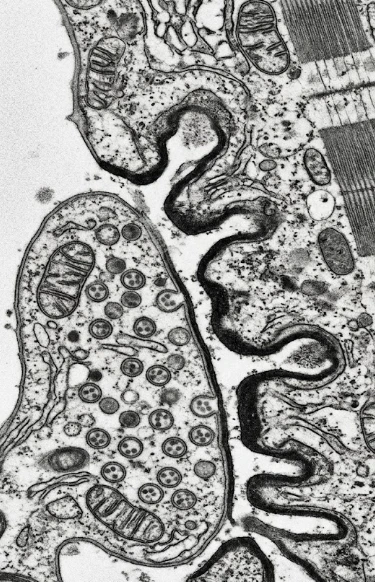

El estudio de mayor precisión diagnóstica para evaluar la comunicación entre el nervio y el músculo.

Es la técnica de referencia para enfermedades de la unión neuromuscular.